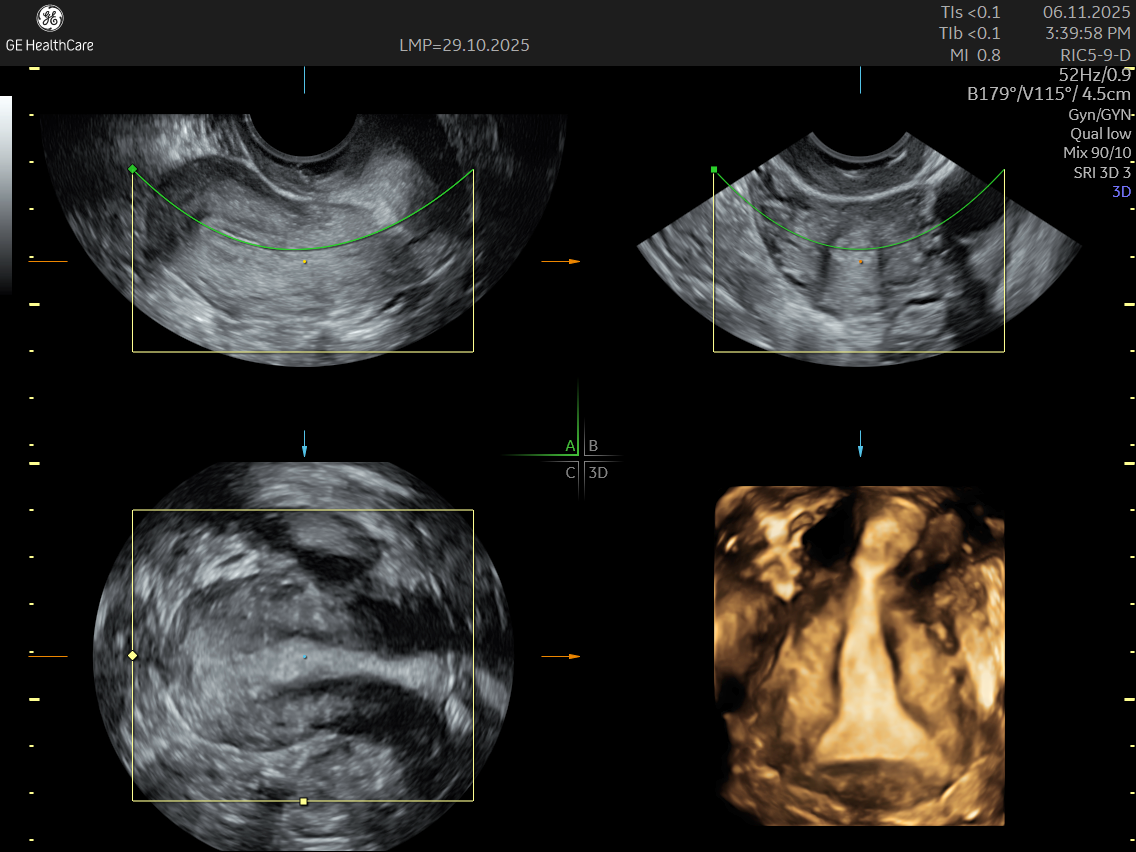

Traditional ultrasounds can miss small or deep infiltrating endometriosis. Advanced gynecological ultrasound, however, combines high-frequency probes, 3D/4D imaging, and specialized Doppler evaluation to provide detailed visualization of the uterus, ovaries, and pelvic structures.

- 3D volumetric scans for a complete anatomical overview

- Color Doppler mapping to study blood flow changes in affected tissues

- Access to 3D/4D ultrasound technology and advanced probe systems